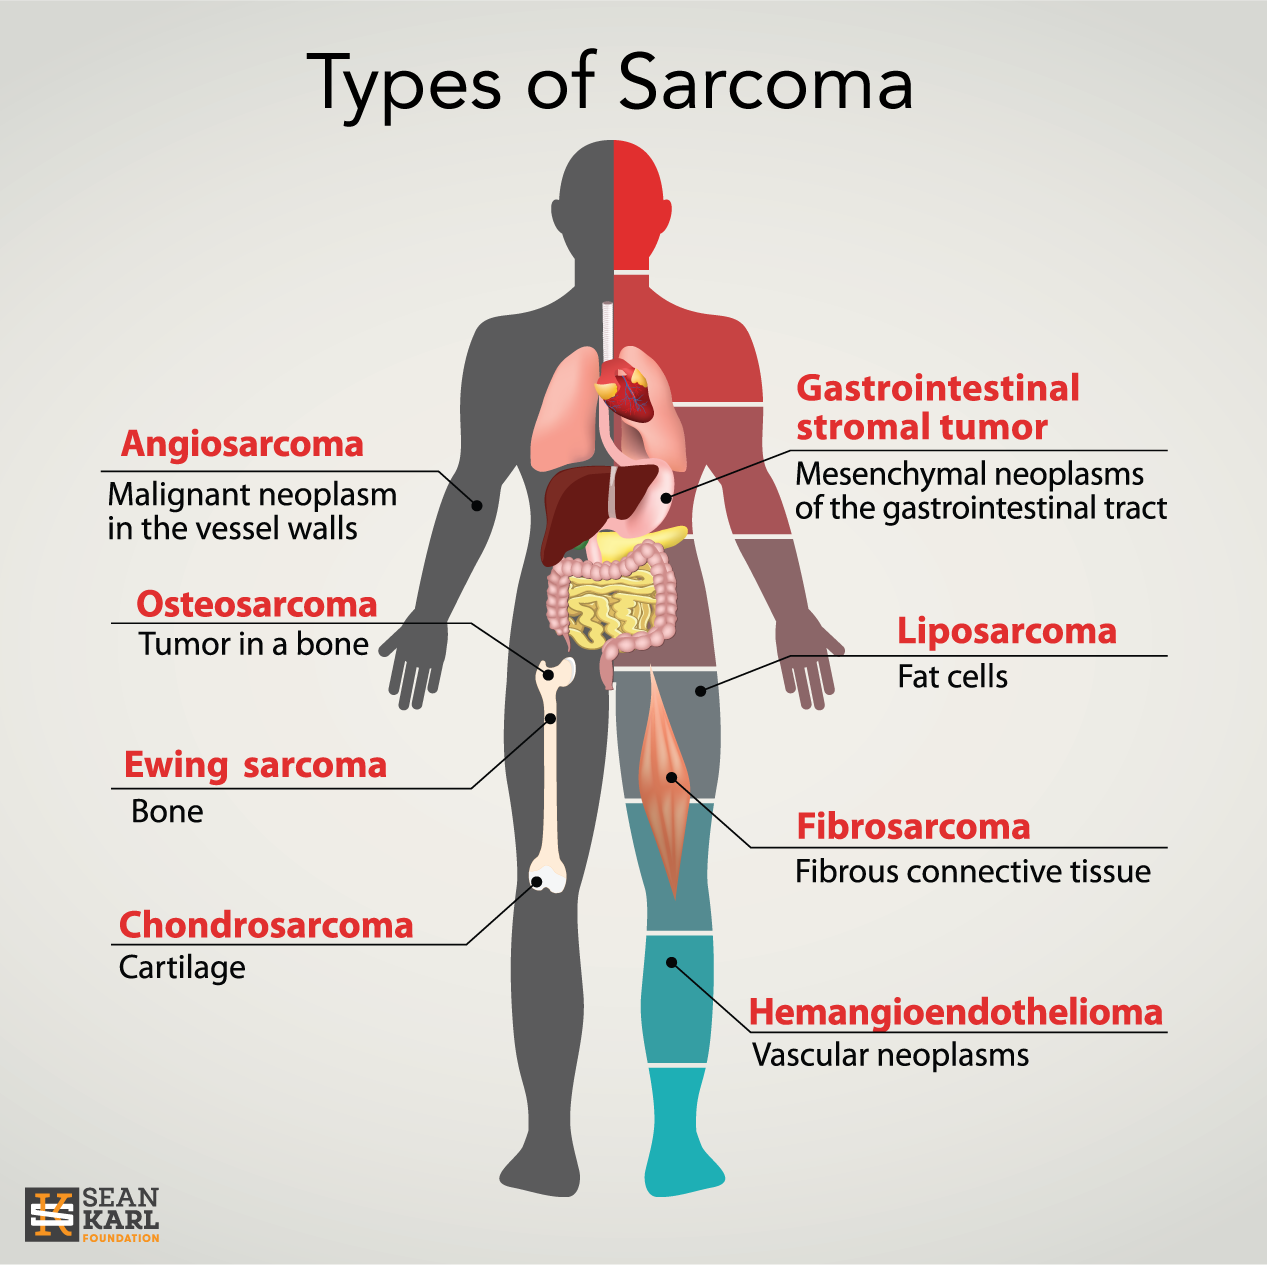

https://seankarlfoundation.org/wp-content/uploads/sarcoma-types.png

Other Names For Soft Tissue Sarcoma

Other Names For Soft Tissue Sarcoma